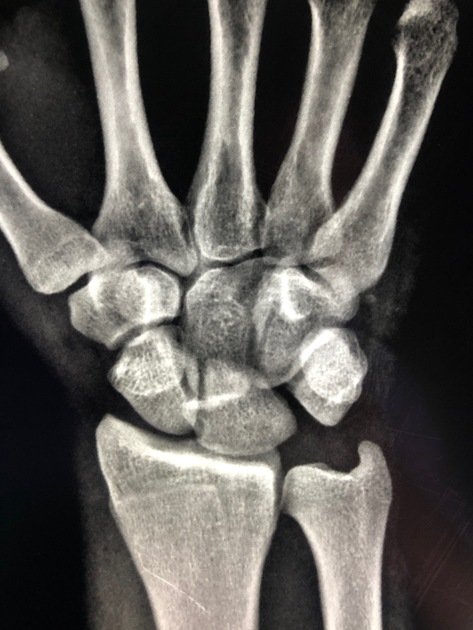

• Gilula`s three carpal arcs (AP view): on a standard PA wrist radiograph in neutral position, three smooth continuous arcs should be identifiable; Arc I — the proximal convex surfaces of the scaphoid, lunate, and triquetrum (a smooth curve); Arc II — the distal concave surfaces of the scaphoid, lunate, and triquetrum (parallel to Arc I); Arc III — the proximal convex surfaces of the capitate and hamate; in a normal wrist, all three arcs are smooth, continuous, and parallel; ANY disruption, step-off, or discontinuity in these arcs indicates carpal instability or dislocation; in a perilunate dislocation, Arcs I, II, and III are all disrupted and the carpal bones overlap each other on the AP view creating a `crowded` appearance

• Key radiological signs summary: (1) AP view — loss of Gilula`s arcs; Terry Thomas sign (SL gap >3 mm); cortical ring sign (foreshortened scaphoid); triangular `pie-slice` lunate; overlapping carpal bones; (2) Lateral view — loss of the normal colinear radius-lunate-capitate alignment; DISI pattern (scapholunate angle >70°, capitolunate angle >30°); the capitate is dorsal to the lunate (perilunate) OR the lunate is volar to the capitate (lunate dislocation — `spilled teacup`); (3) AP + Lateral combined — the lateral view is the single most important view for diagnosis; most missed diagnoses are due to failure to examine the lateral view carefully

• Plain radiographs: AP, lateral, and oblique views of the wrist are the mandatory initial investigation; the lateral view is the most diagnostically important — examine carefully for the radius-lunate-capitate alignment; the AP view demonstrates Gilula`s arc disruption; the diagnosis is frequently missed because: (1) the AP view may appear confusingly `crowded` rather than obviously abnormal; (2) the lateral view is not examined carefully; (3) the treating clinician is not familiar with the normal carpal relationships; a systematic approach to every wrist X-ray (check Gilula`s arcs on AP; check R-L-C alignment on lateral) prevents missed diagnoses

Image credits: Sarlo L, Perilunate dislocation. Case study, Radiopaedia.org (Accessed on 18 Mar 2026) https://doi.org/10.53347/rID-72054